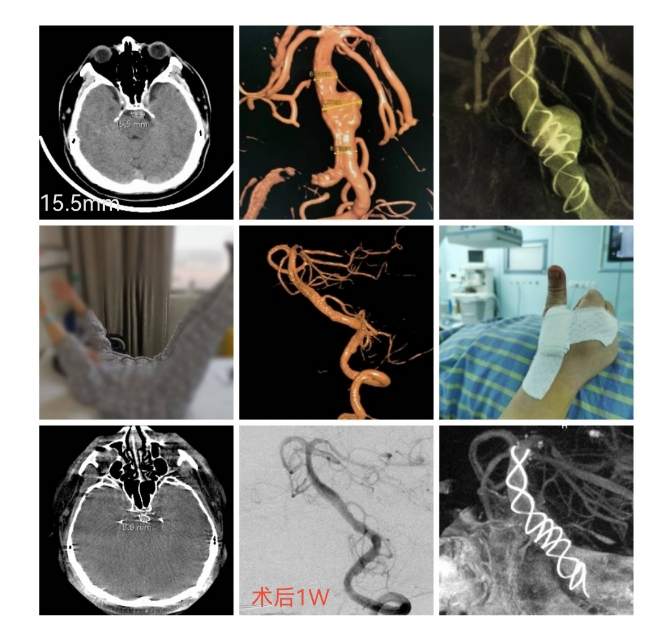

椎基底动脉冗长扩张症,是最棘手最复杂的脑血管病之一。患者从外地千里迢迢(3900余公里,仅高铁41小时)赶来东方医院诊治,期间症状不断加重(图2非真实大小)。术后一周复查:1、右侧肢体肌力明显改善;2、右侧肢体和枕部麻木症状明显改善;3、饮水呛咳缓解;4、共济失调明显改善;5、流涎消失;6、消失的味觉再次恢复。术后一周复查:血管修复良好(图5)。期待患者早日康复,早日奔赴工作岗位,保一方平安。